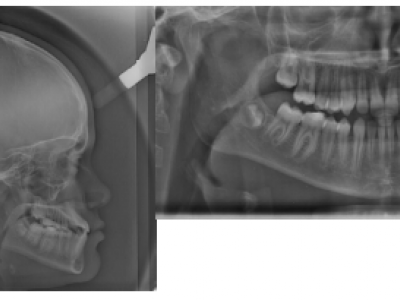

- Le second cas est un enfant de 6 ans 4 mois consultant pour une prognathie mandibulaire (Fig. 10).

La mandibule circonscrit le maxillaire en avant et vers la droite. Comme le maxillaire est inscrit dans la mandibule à droite avant tout contact prématuré générant une déviation, le décalage transversal est déjà visible sur la photo de face, en position de repos. Le sourire découvre les dents inférieures, et s’apparente à un rictus. L’occlusion montre une endognathie et une rétrognathie maxillaire avec prognathie et latérognathie mandibulaire droite.

La projection mandibulaire est toujours plus marquée sur la téléradiographie qui est en occlusion (Fig. 11-16), que sur la photo, en position de repos, donc en inocclusion, avec une situation un peu plus reculée de la mandibule. Sur la radiographie panoramique, le manque de place est plus important à l’arcade supérieure, témoignant du manque de développement de cette structure. L’expansion tridimensionnelle de l’arcade donnera de la place aux dents permanentes.

- Le traitement du deuxième cas a commencé par un appareil à plans molaires d’une hauteur importante, pour une expansion transversale et antérieure du maxillaire. Grâce à cette surélévation de l’occlusion, le surplomb maxillaire est obtenu, un élastique de classe III est mis à gauche pour aider le recentrage.

Quand les dents supérieures recouvrent les inférieures (Fig. 12), la hauteur des cales est progressivement diminuée pour ne pas laisser de béance latérale. Les incisives centrales maxillaires sont rapprochées pour donner la place aux latérales, et les brackets mandibulaires améliorent le recouvrement et la position des incisives inférieures. Sur la photo, les cales ont déjà été diminuées (Fig. 12) de plus de la moitié de leur hauteur efficace de départ.

Les bagues et l’appareil sont ôtés 3 mois plus tard (Fig. 13), en juin, pour les vacances d’été, puis le patient est revu à la rentrée de septembre (Fig. 14).

Pour le second cas, on note que grâce au traitement, le visage a retrouvé une harmonie et une symétrie.

Après traitement le patient ne sourit plus avec les dents inférieures, mais avec les incisives supérieures (Fig. 13).

La plaquet à surélévations a permis le repositionnement correct du maxillaire par-dessus la mandibule, et des attaches collées antérieurement ont aligné les dents. Le manque de place pour les dents définitives s’est spontanément amendé (Fig. 14).

Le patient est revu en denture définitive à 12 ans 9 mois (Fig. 15) avec un bilan radiologique (Fig. 16), pour entreprendre une finition multiattache, les résultats orthopédiques obtenus précocement se sont maintenus.